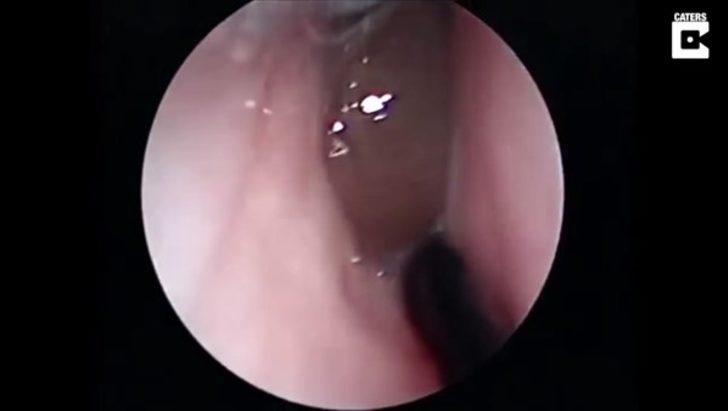

Burnunda garip bir hareketlilik hisseden hasta doktora göründü.

Doktor ise ufak bir operasyon yaptı.

Yüzerken burnuna kaçan şey doktorları bile şaşırttı